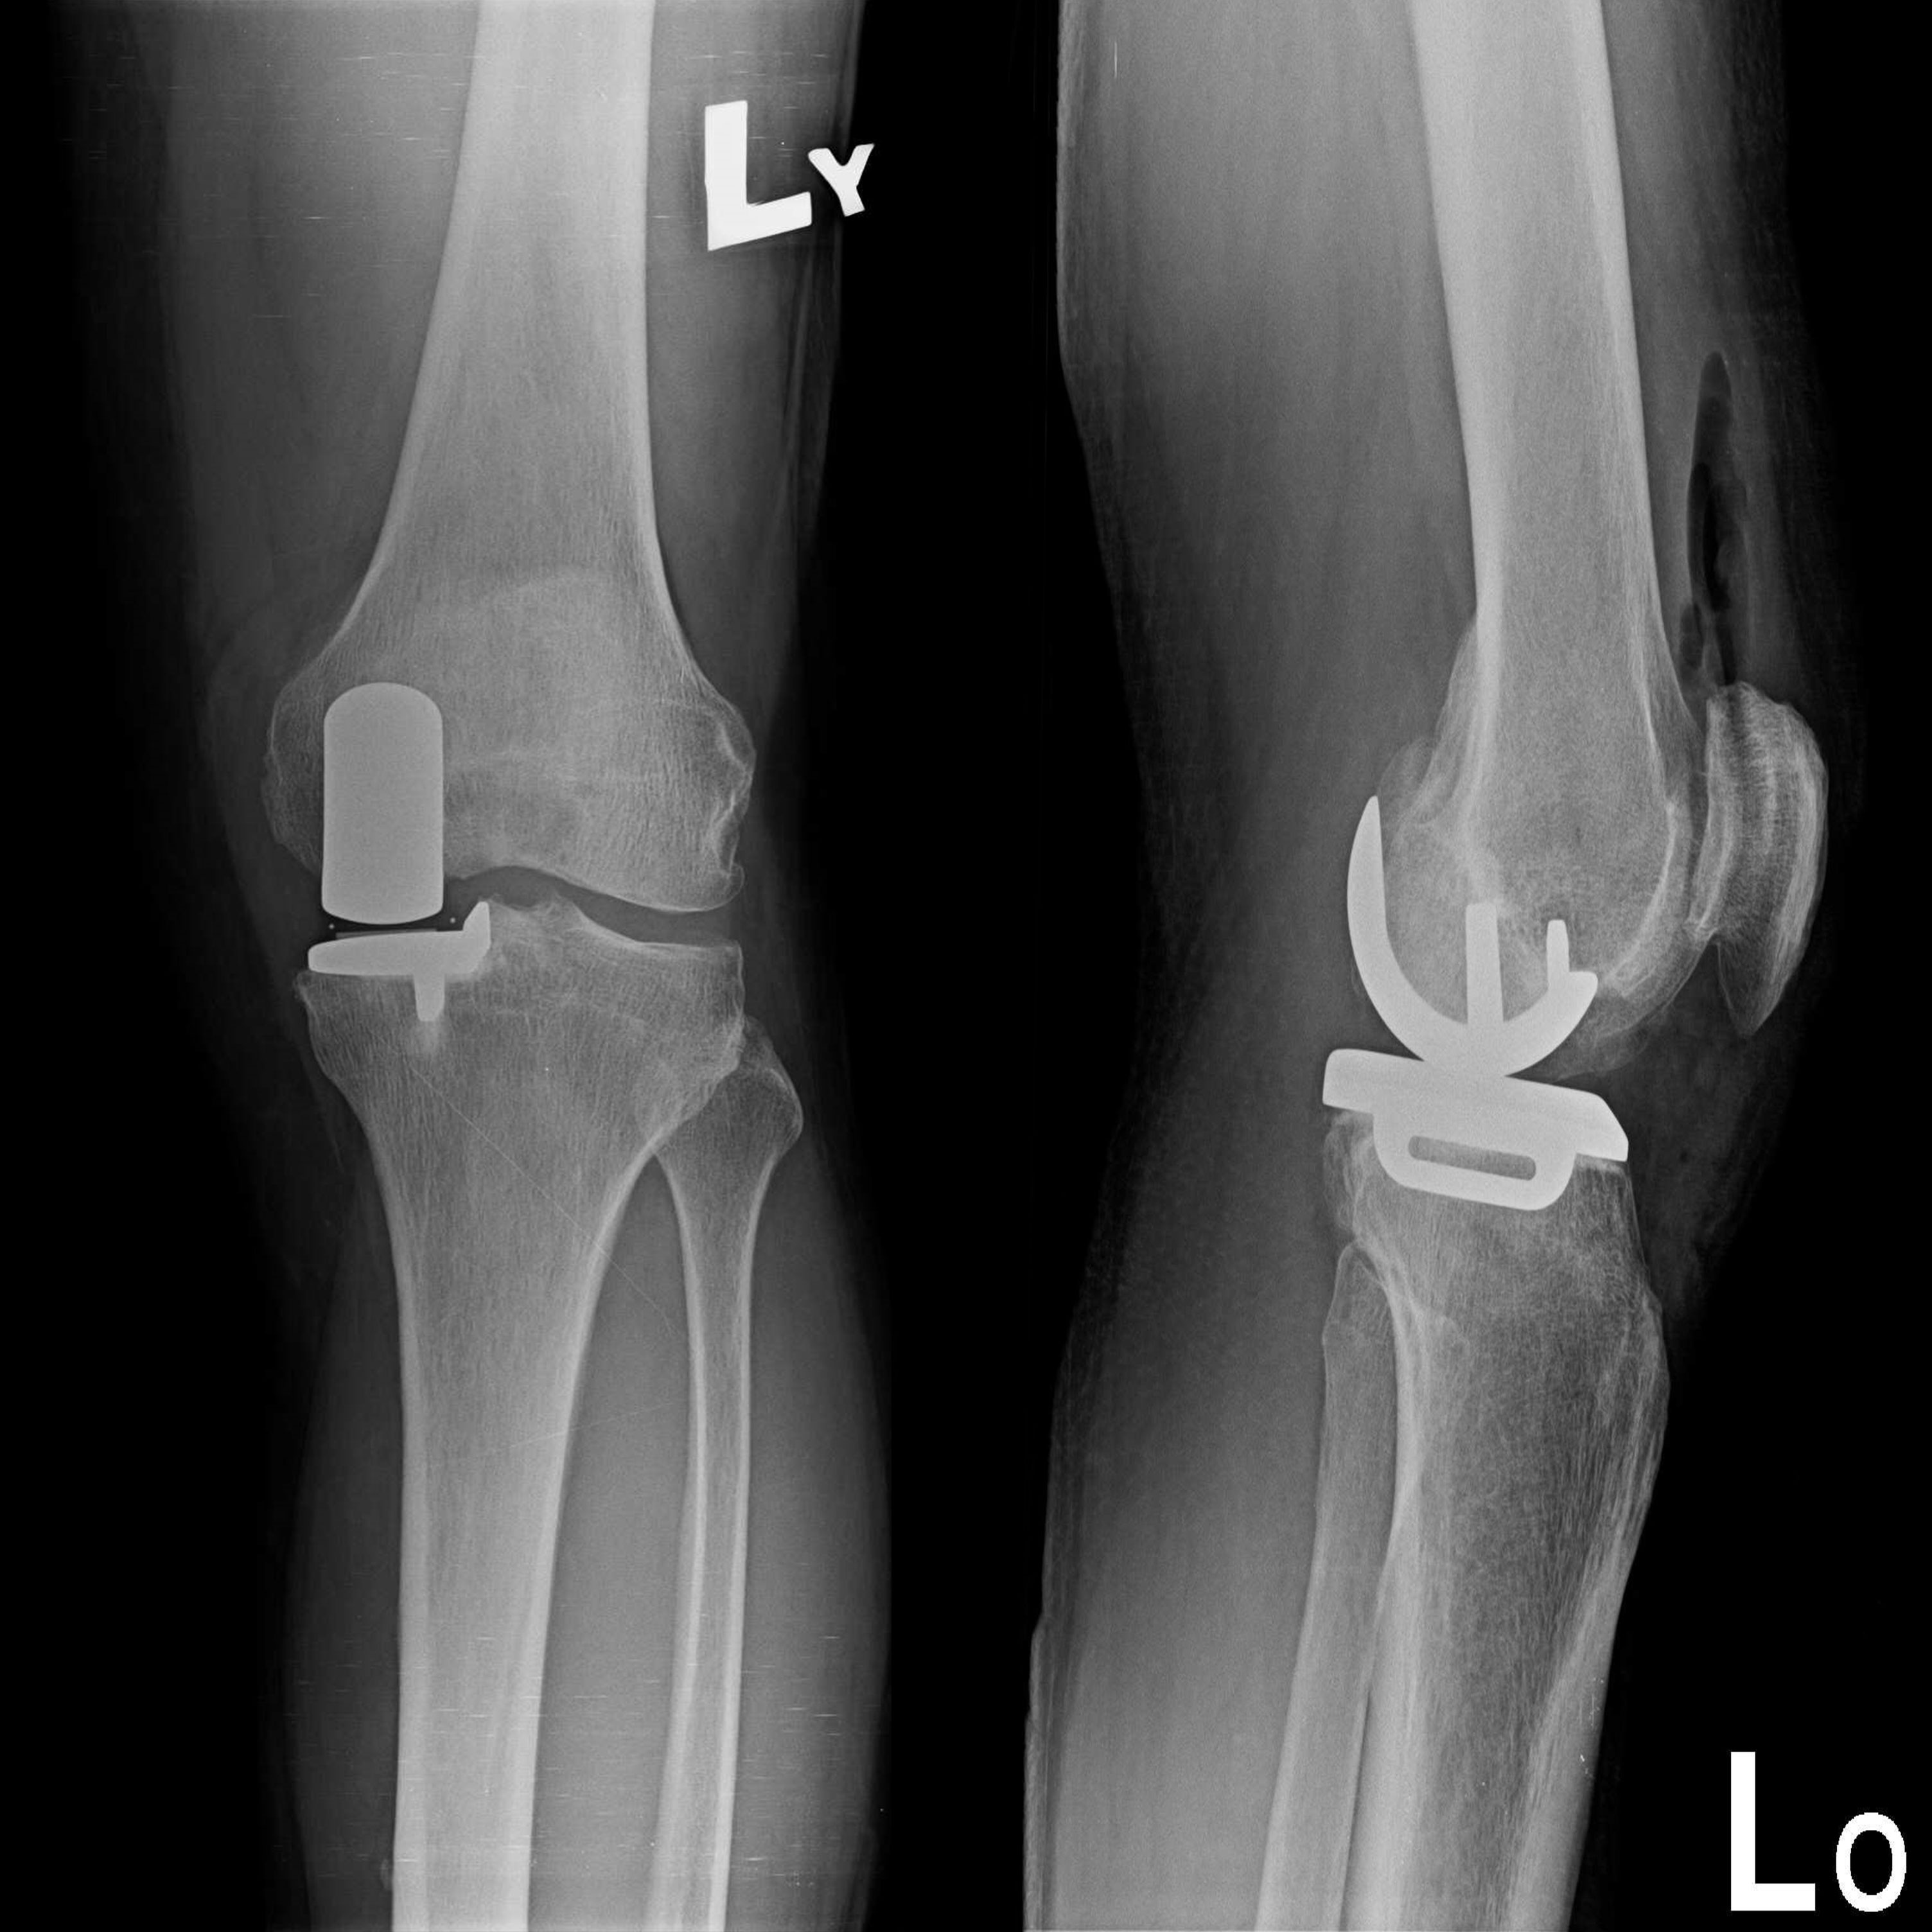

傳統部分膝置換 首頁 案例分享 膝關節手術 傳統部分膝置換 殷女士 65歲 術前 術後 張女士 71歲 術前 術後 蔡女士 74歲 術前 術後 張女士71歲 術前 術後 翁女士70歲 術前 術後 劉女士 80歲 術前 術後